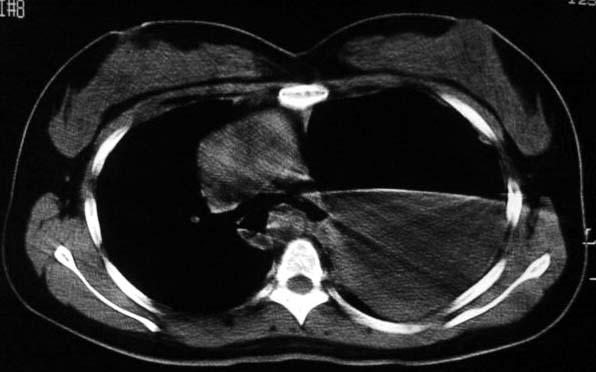

标题: CT5517:女性、24岁,反复胸痛、气促不能平卧半月。 [打印本页]

标题: CT5517:女性、24岁,反复胸痛、气促不能平卧半月。

左肺可见二个含气或液气的囊状影,左肺段支气管、左肺动脉显示不清,纵隔右移,考虑:左肺支气管肺囊肿,左肺发育不良,纵隔疝。

我看这是膈疝,在纵隔窗第六\\七幅图像上可见胃粘膜影,再者可见两个腔影,这在液气胸是不会有的.

综合分析考虑:1左侧包裹性液气胸。2左侧胸膜肥厚。3左肺膨胀不全

不排除先天畸形,1.左肺支气管肺囊肿,左肺发育不良,2.左纵隔先天畸形?3.胸腔胃?